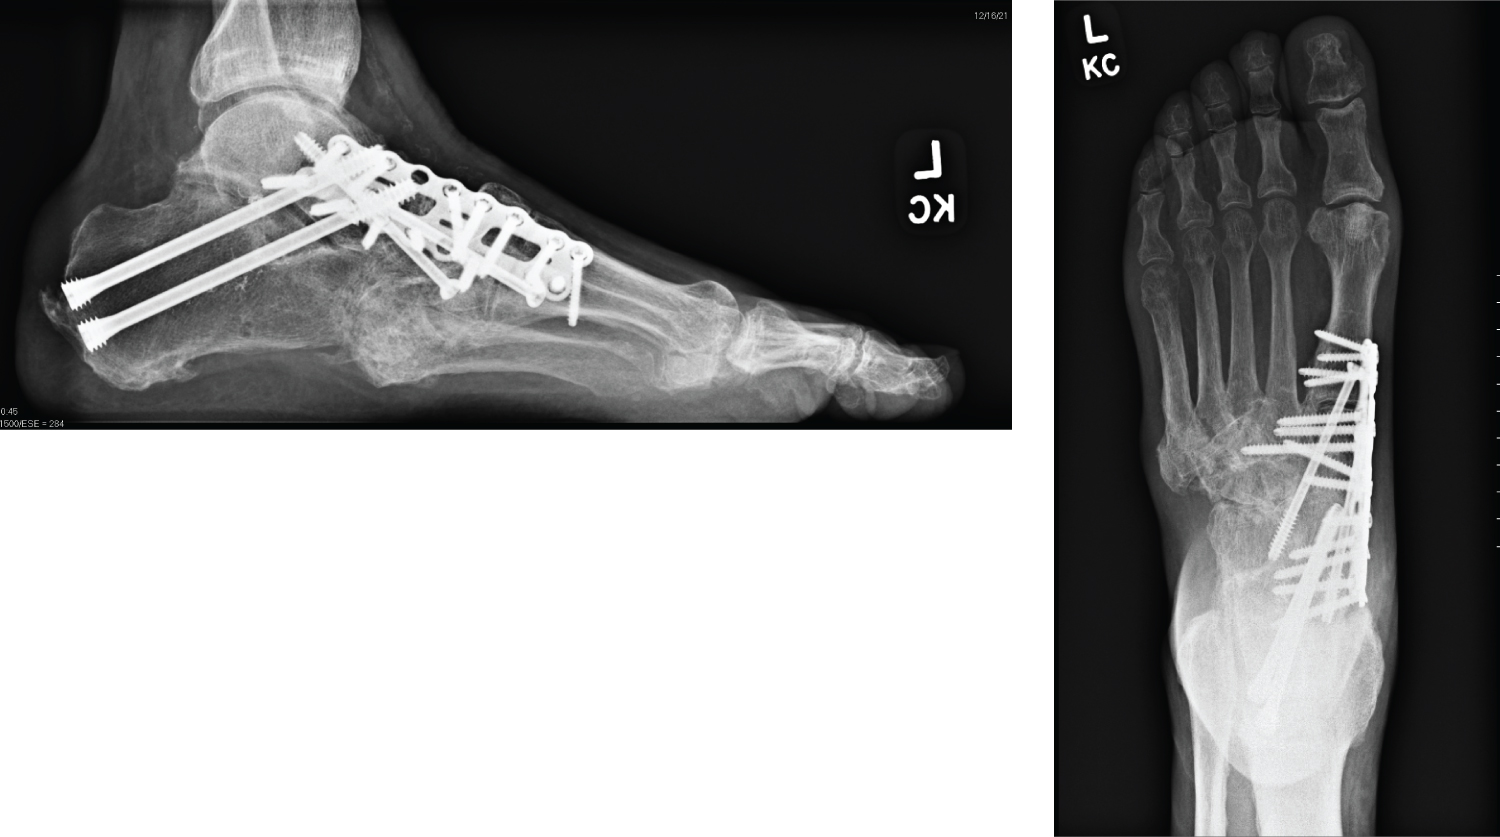

Once positioning is confirmed and accurate, rigid internal fixation can be placed across the osteotomy in a superconstruct fashion. The use of beaming, plating, and multiple screws is recommended here (Figure 5).

Figure 5: Final fixation. View Figure 5